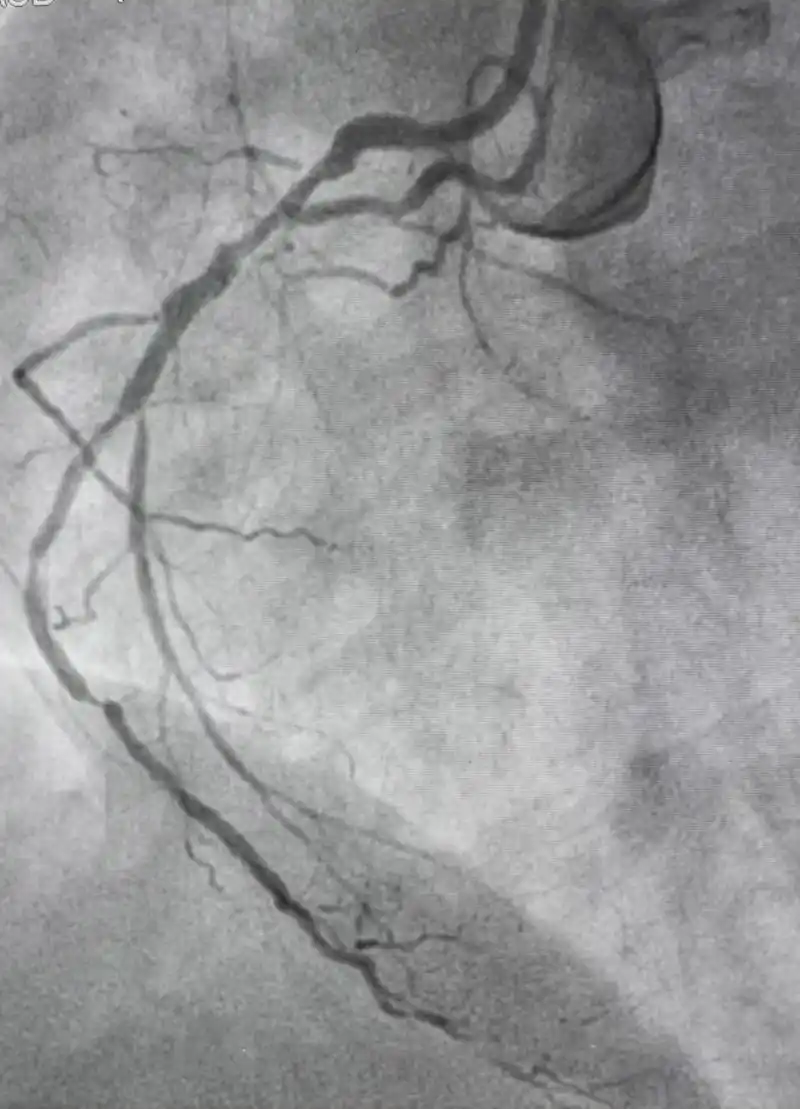

🤔冠状动脉造影术后,患者朋友们最关心的就是如何快速恢复.